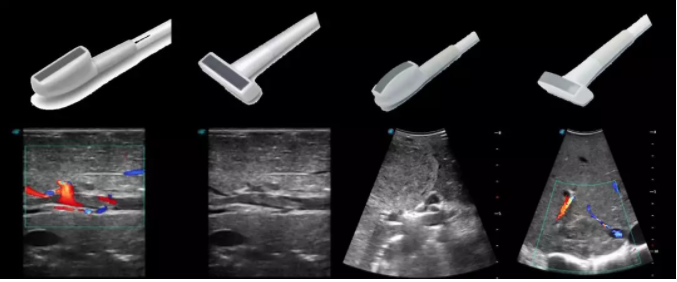

線陣/凸陣不同選擇,多種外形設計可以滿足適用于不同的臨床科室,滿足不同醫(yī)生的使用需求;

輕便小巧,方便持握;

防水、易消毒;

應用科室:手術室、肝膽外科、消化外科、腫瘤科、心胸外科、泌尿外科、婦產科等